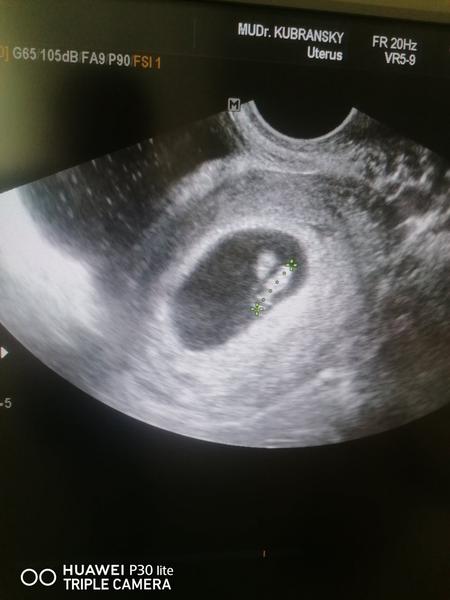

@ursula27 dám ti moju skúsenosť mne až v 12tt na 3D povedal dr že som čakala dvojičky.Moja dr to nevidela môj muž trdil že vidí dva vaky a mal pravdu.Jedno sa mi prestalo vivijat medzi 6-8tt to už nik nezistí kedy presne.A dnes mám zdravú 5mes dcérku.Komlikacie neboli žiadne.Bud ide o zaniknuté dvojča a druhé babo je zdravé alebo sa z toho vivinu dvojky zdravé.Kazdopadne držím palce pridávam môj obrázok z prvého sona